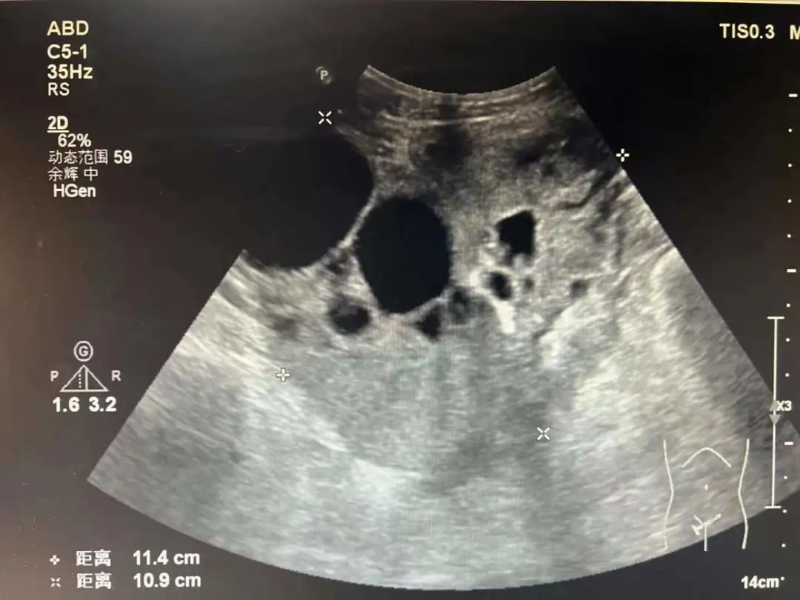

3月16日,超声医学科主任陈勇辉主任医师为马女士进行超声引导卵巢肿瘤穿刺活检,陈勇辉通过超声扫描对病变进行精准测量、定位,选择最佳穿刺点,经过局部麻醉后,用穿刺针切割病变活性组织,送至病理科检查。经检查后马女士确诊卵巢浆液性囊性癌,有了超声医学科的精准穿刺活检,为马女士后续诊疗打下良好基础。